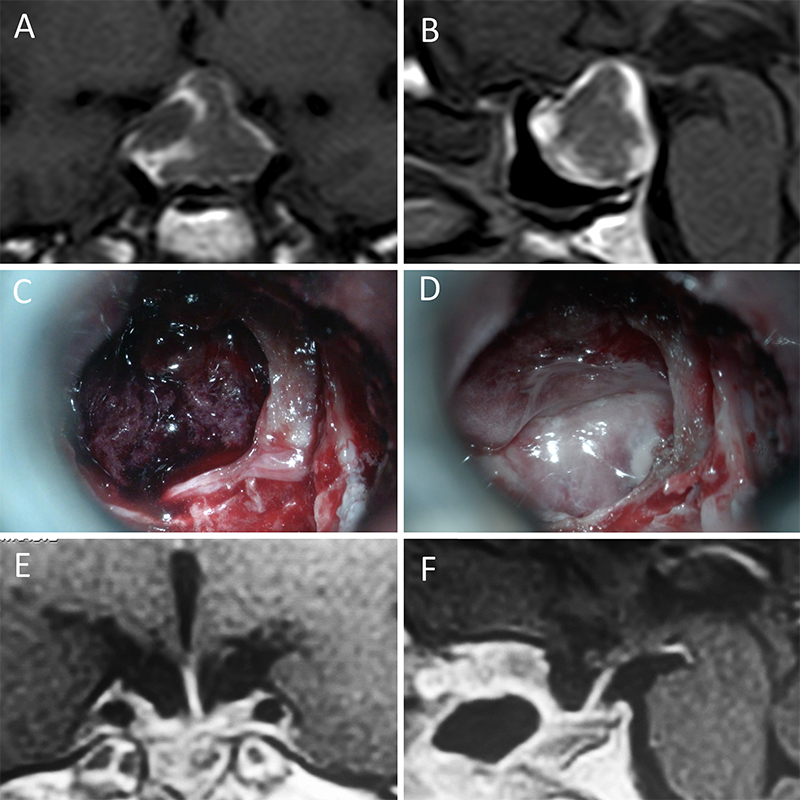

Figura 1: Macroadenoma no funcionante en mujer de 65 año s. Se decidió la cirugía tras evidenciarse crecimiento en los controles. Evolucionó favorablemente desde el punto de vista clínico-radiológico. A-B: RM preoperatoria; C-D: intraoperatorio; E-F: RM postoperatoria.

Figura 2: Macroadenoma no funcionante en mujer de 31 años. La paciente presentó en el preoperatorio déficit visual que mejoró tras la cirugía. A-B: RM preoperatoria; C-D: intraoperatorio; E-F: RM postoperatoria.

Figura 3: Macroadenoma no funcionante en un hombre de 64 años. El paciente presentó en el preoperatorio déficit visual que mejoró tras la cirugía. A-B: RM preoperatoria; C-D: intraoperatorio; E-F: RM postoperatoria.

Figura 4: Macroadenoma no funcionante en mujer de 32 años. La paciente presentó en el preoperatorio déficit visual que mejoró tras la cirugía. A-B: RM preoperatoria; C-D: intraoperatorio; E-F: RM postoperatoria.